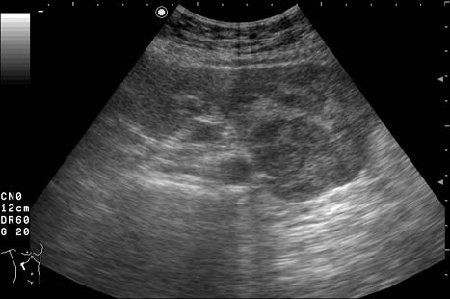

Женщина 72 лет. При УЗИ выявлены два аваскулярные образования: в нижнем полюсе правой почки и у верхнего полюса почки.

Уникальность случая в том, что эти изменения - БЕЗ ДИНАМИКИ с 2005 года.

Опухоль почки?

Опухоль почки и надпочечника.

Без допплера явно опухоль почки